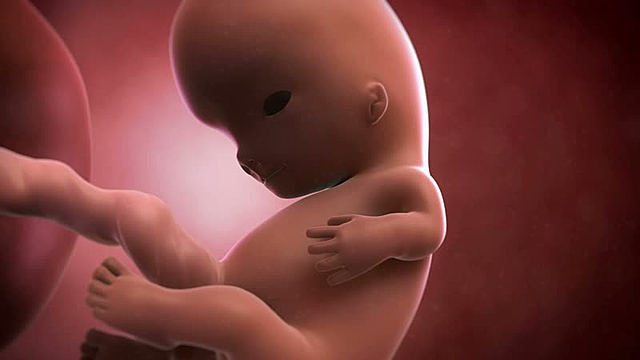

• Semana 32

Semana 32

Algunos bebés ya tienen cabello y un fino bello por todo su cuerpo, la piel se torna suave y lisa el bebé ocupa todo el espacio en el vientre